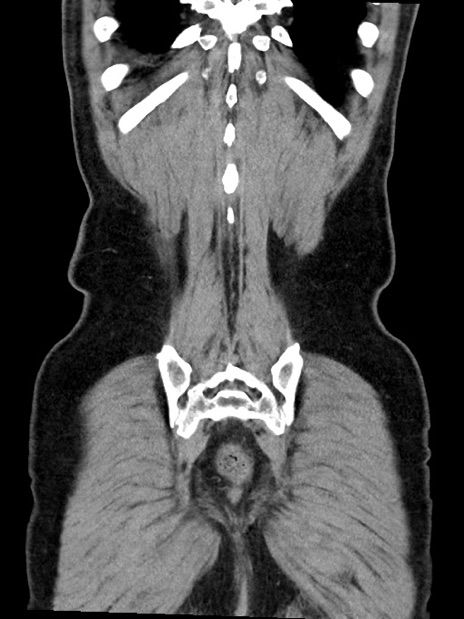

症例35(冠状断像)

【症例】70歳代 男性

【主訴】腹部膨満、嘔吐

【現病歴】昨日より腹部膨満感出現。本日増悪し、仙痛出現。嘔吐あり、受診。

【既往歴】糖尿病、胆摘後

【身体所見】BP 149/80mmHg、HR 74/min、BT 35.9℃、腹部:膨満、軟、圧痛なし。腸雑音減弱あり。上腹部正中切開瘢痕あり。

【データ】WBC 13500、CRP 1.72